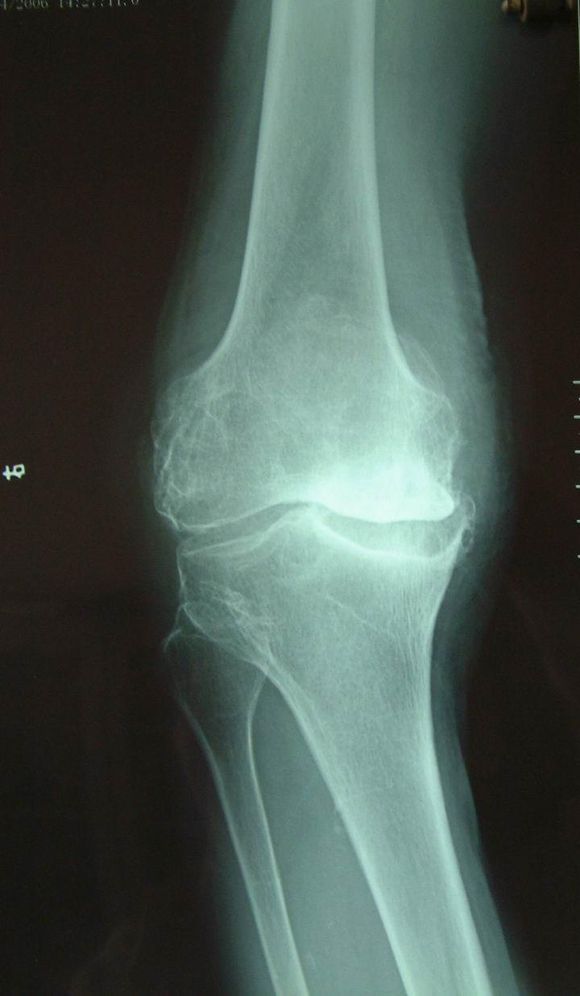

图3.膝关节重度骨关节炎